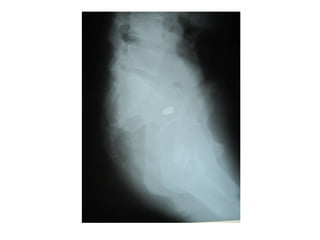

ชายไทยอายุ 28 ปี ถูกยิงที่ชายโครงด้านซ้าย 50

นาทีก่อนมารพ.

Gun shot wound at intercostal space 9-10 size 0.5cm

Back: gun shot wound(ทางออก) size 1 cm level

T11-T12